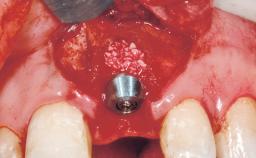

A 42-year-old female patient was referred to our clinic at the School of Dentistry of the University of São Paulo in November 2004, presenting a deficient restoration in the upper left central incisor. The clinical examination revealed no gingival retraction or any signs of gingival inflammation and, therefore, previous periodontal treatment was not considered. The patient presented a high lip line at full smile and a thin tissue biotype. This combination characterized a high-risk situation from an anatomic point of view, which required careful preoperative planning and cautious surgical execution.

Placement Protocol Immediate implant placement

Tooth Site Maxillary incisor or canine

Socket Morphology Single-root socket

Socket Integrity Sufficient, with intact bone walls

Bone Volume Sufficient, with intact walls